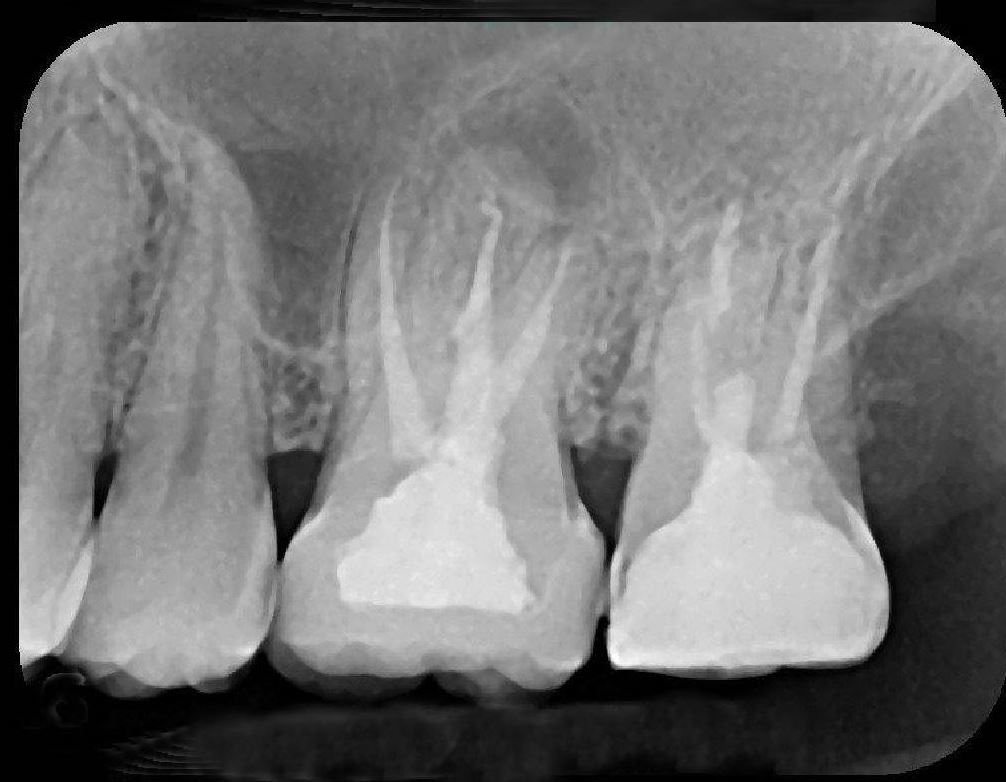

X-Ray 5: How many caries are present?

(Required)

X-Ray 5: How many PAP's are present?